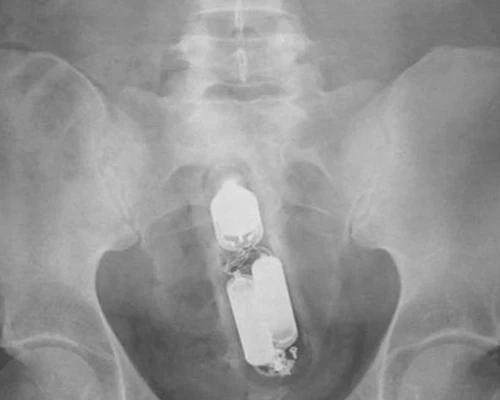

Инородное тело в прямой кишке: полное руководство по симптомам и лечению

Столкнулись с деликатной и пугающей проблемой инородного тела в прямой кишке? Наша статья подробно описывает все симптомы, объясняет методы диагностики и безопасного извлечения предмета врачом, а также рассказывает о последствиях.